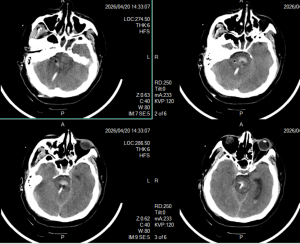

2026年4月29日 Home立体定向技术脑干出血急诊穿刺引流,抢救生命 脑干出血急诊穿刺引流,抢救生命 By admin 立体定向技术 0 Comments 病人1,4月13日急性脑干出血,迅速神志不清 术前CT显示脑干出血 脑干出血发病时 手术计划 术后复查,显示定位准确,穿刺道完全符合术前计划 术后7天,血肿基本引流干净 手术后15天情况 现病人生命体征平稳,正在促醒康复中 About Author admin Add a Comment 取消回复您的邮箱地址不会被公开。 必填项已用 * 标注Comment:*Name:* Email Address:* Website: Save my name, email, and website in this browser for the next time I comment. Δ